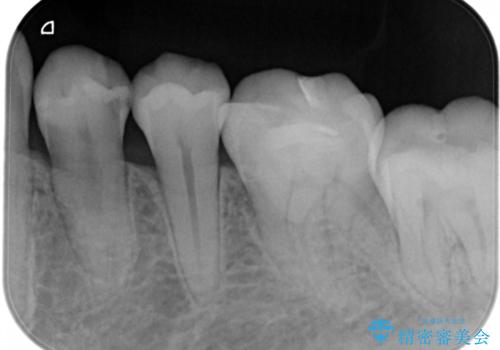

- 左下4番のう蝕を指摘され治療を希望された患者様です。

切削量などを考慮しクラウンでの治療を提案したところ、セラミックを希望されたのでフルジルコニアクラウンでの治療を選択しました。

う蝕が深かったので痛みが出る可能性をお伝えしましたが特に症状は現れなかったので、予定通りセラミッククラウンでの治療を行いました。